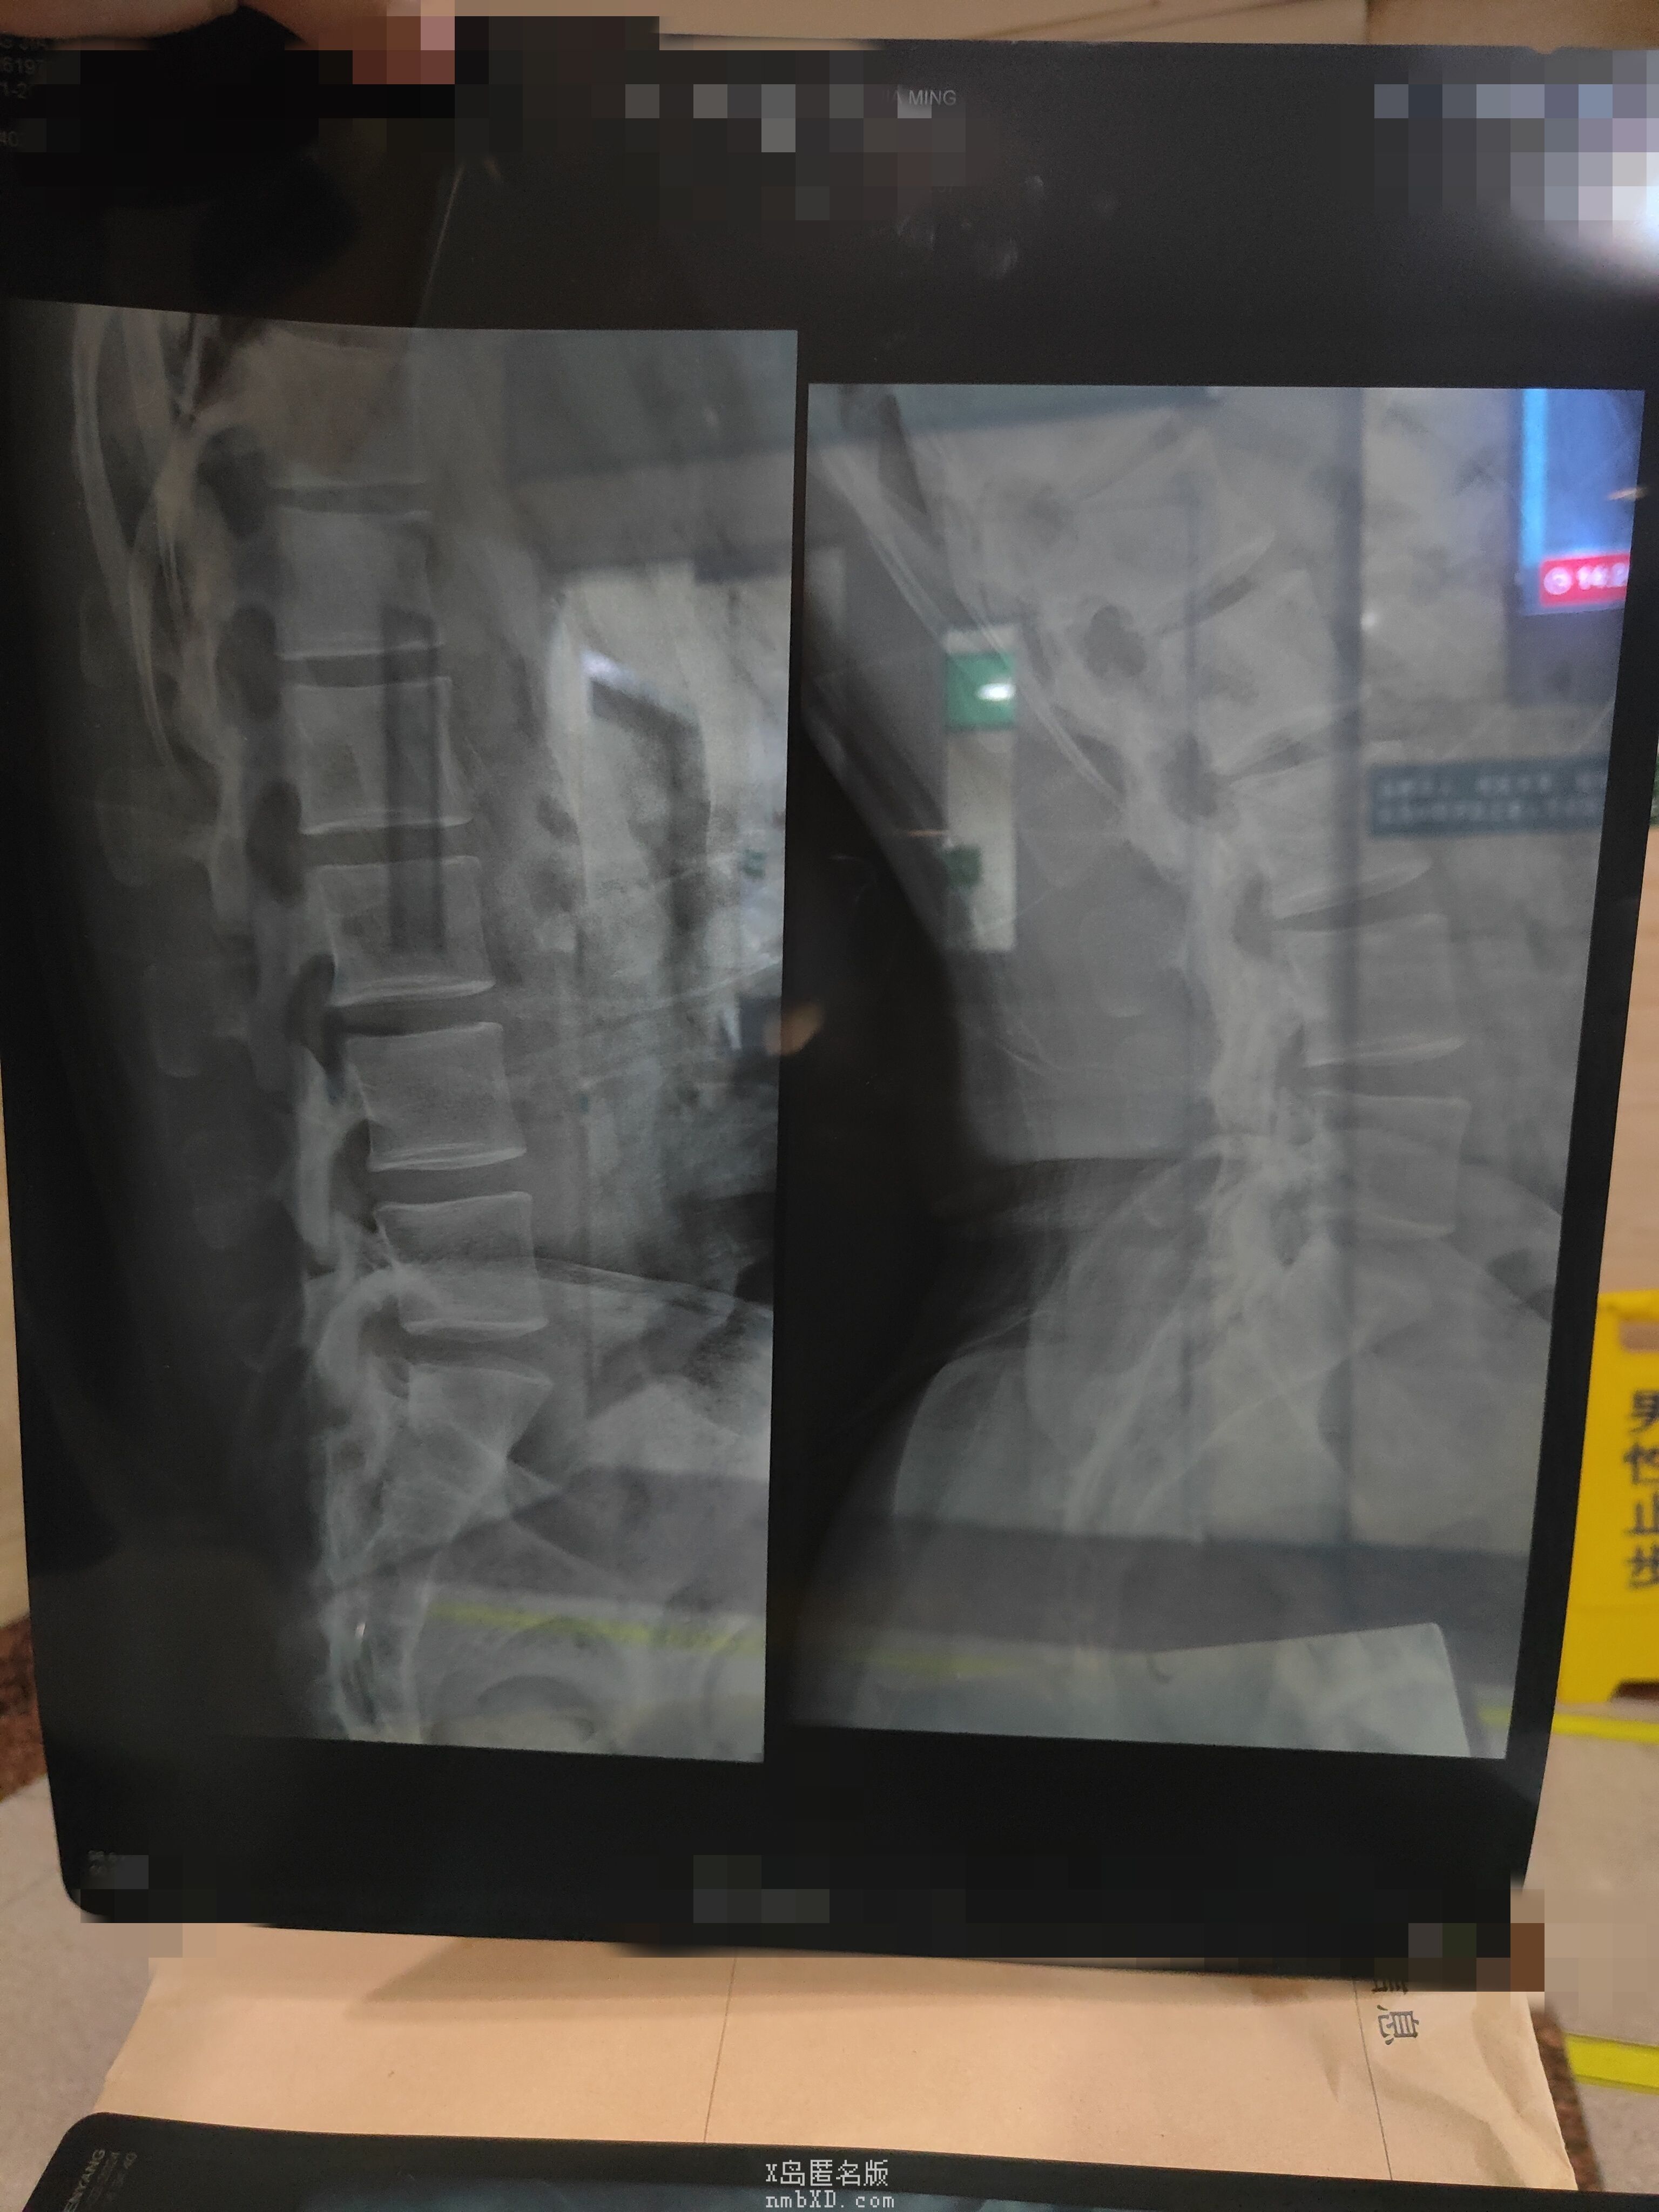

片子来力

收起 查看大图 向左旋转 向右旋转

有点点明显了已经,平常会不会下背痛,腰背累,晨僵之类的

没有什么感觉啊(|||゚Д゚)

或者是我已经莫名其妙的适应了,现在察觉不到?

没感觉的话不管先,不过平常注意矫正姿势,坐正睡平,也千万不要去按摩店

硬举先不做先,卧推什么的可以,深蹲这种也儘量少一点(`・ω・)